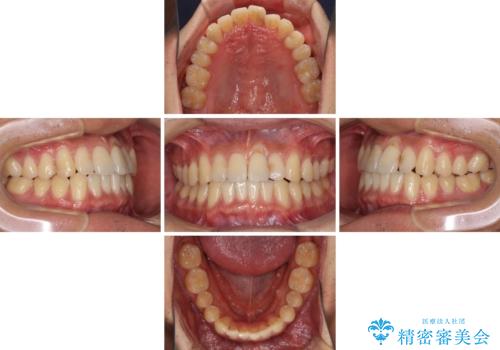

気になる前歯のデコボコをインビザラインで解消

- 前歯のデコボコを気にして来院された患者様です。

主に下顎歯列全体の後方移動とIPR(歯と歯の間を削る)によってデコボコが解消するように設計し、インビザラインにより治療を行うこととしました。

インビザライン矯正特有の、治療後半で前歯のみが強く接触する症状が発現し、咬み合わせ改善に期間を要することとなりました。